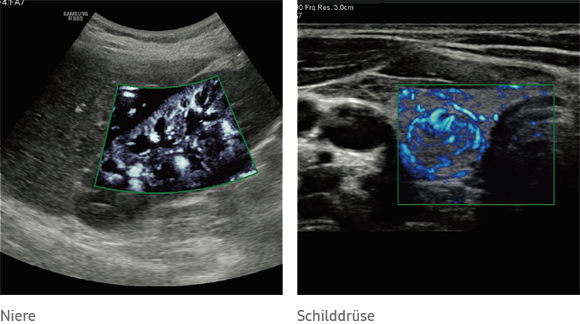

MV-Flow™

MV-Flow™ offers you an alternative to color doppler for the visualization of slow flows. High frame rates and advanced filtering techniques allow a detailed view of blood flow in relation to surrounding tissue or pathology, with improved spatial and temporal resolution.